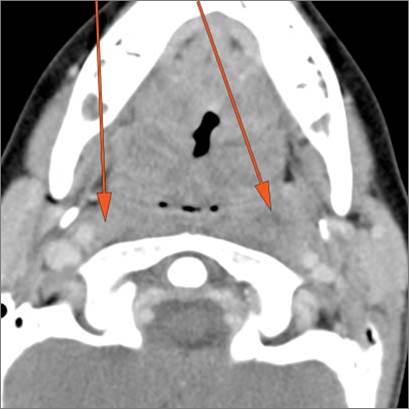

If there is suppurative cervical adenopathy the purulent material outside the lymph node(s) capsule(s).